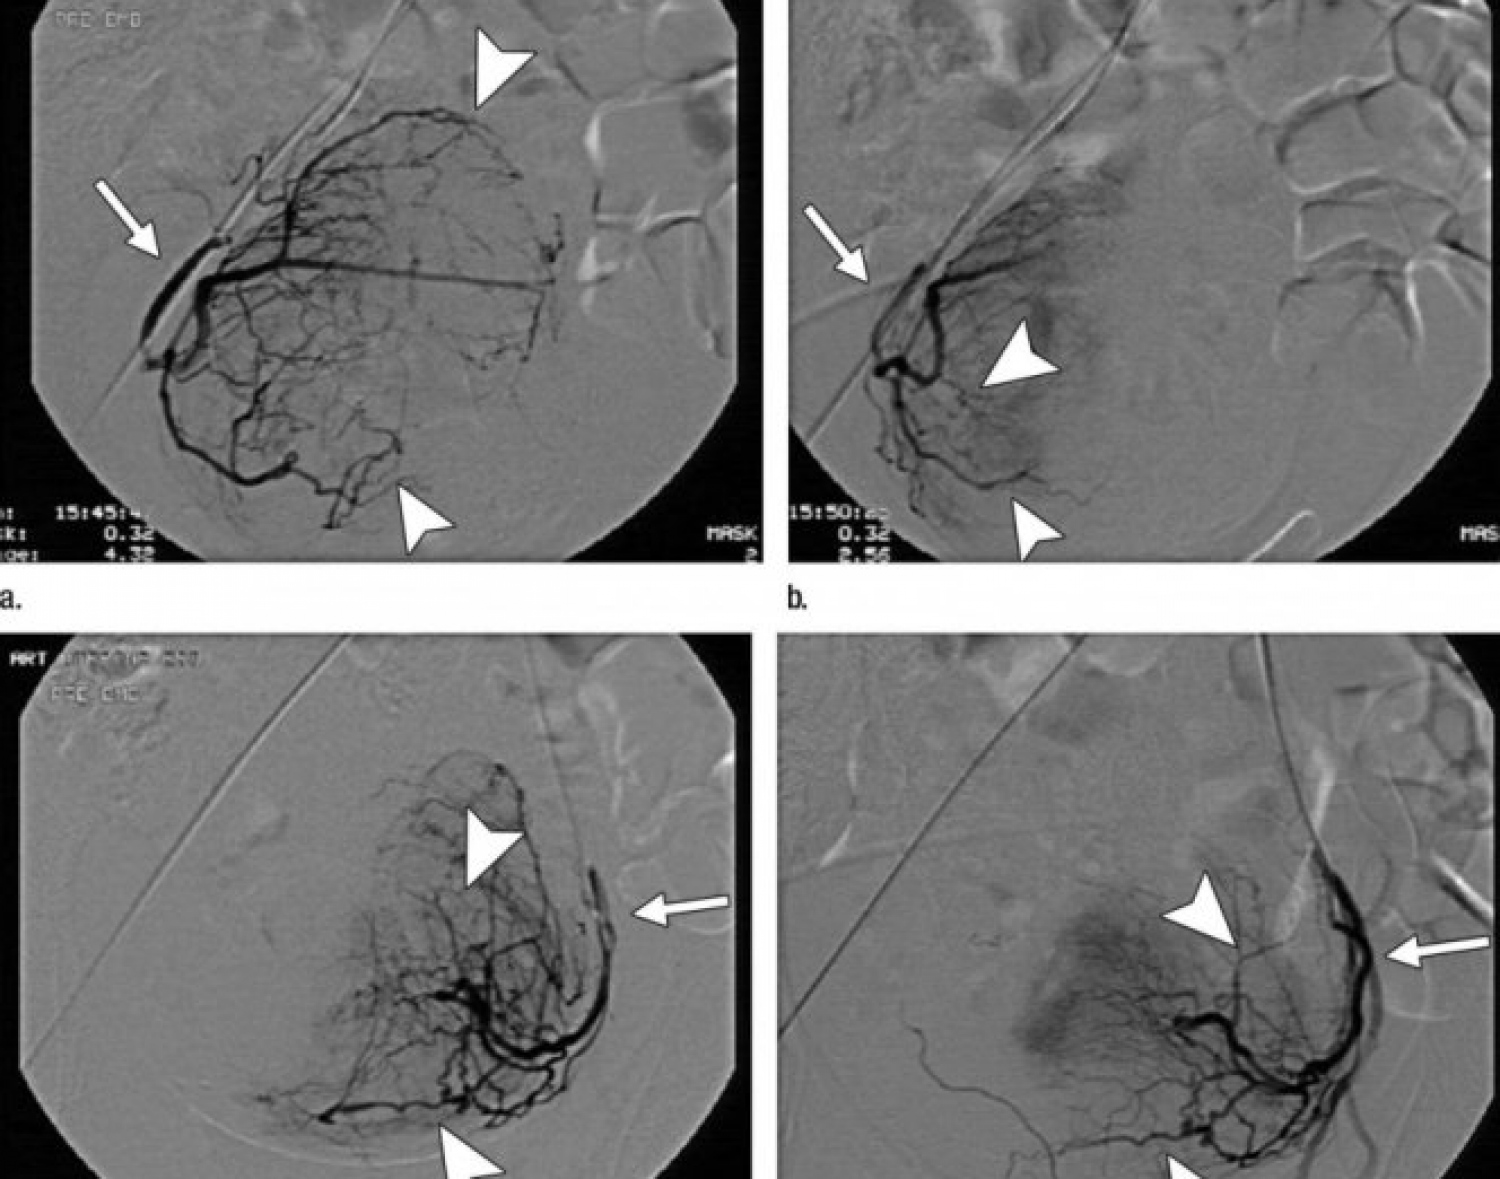

ޕާޝިއަލް ޔޫއެފްއީ އެއްގެ ޑިޖިޓަލް ސަބްޓްރެކްޝަން އެންޖިއޮގްރަފީ އިމޭޖެއް